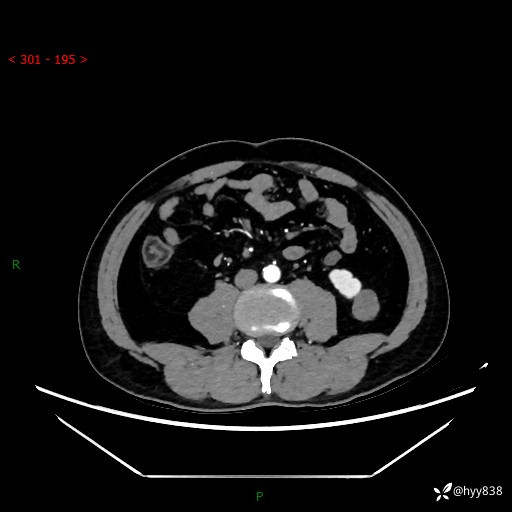

中年男性,左侧腰背部间断性胀痛不适。第一眼“乳头或囊肿”,有无意外---(有结果)

【患者信息】:41岁/男

【主诉】:左侧腰背部间断性胀痛不适1周

【现病史及既往史】:患者1周前无明显诱因出现左侧腰部疼痛,呈间断性胀痛,休息后可缓解,无放射痛,偶可见肉眼血尿,无血块,无尿频尿急尿痛,无夜尿增多,无畏寒发热、咳嗽咳痰等症状。于我院查双肾CT示:左肾占位性病变,左肾下极囊性病变,左肾轻度积水,胆囊多发结石。今为求进一步诊治来我院,门诊以“左肾占位性病变”收治入院。 起病以来,患者精神佳,饮食、睡眠良好,大便正常,小便如上诉,体力体重无明显变化。

【检查】:肾脏CT平扫+增强